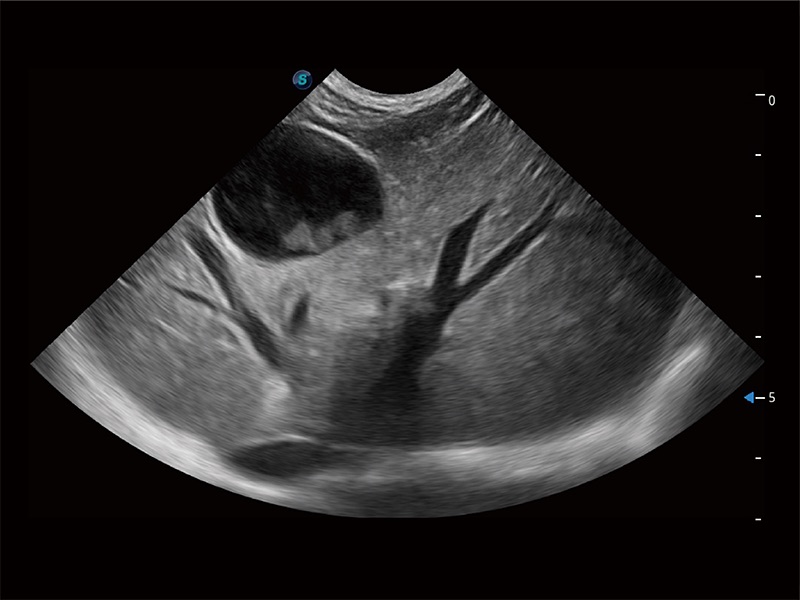

操作简便,无需高频度外力作用即可真实反映组织的形变,快速评估肿瘤良恶性。

非线性融合造影成像充分利用谐波和基波信号,为难以观察的血流进行增强显像。可用于线阵、凸阵、微凸阵、相控阵探头。